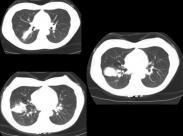

肺隱球菌病

• 肺隱球菌病

628健康網為您分享有關肺隱球菌病的癥狀,肺隱球菌病的治療方法,肺隱球菌病的預防知識,肺隱球菌病的癥狀圖片,肺隱球菌病...